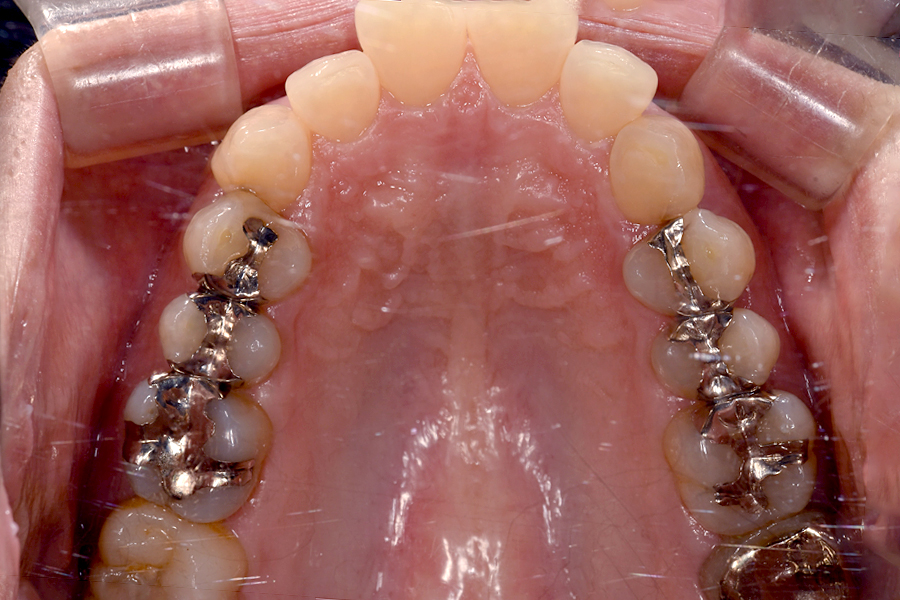

| 見た目 | ×:表側に金具がつく |

| 感覚 | ×:1ヶ月分の力を一気に加えるため痛い 金具が唇にあたり、口内炎などができやすい |

| 食事・日常生活 | ×:食べ物が詰まりやすくなる 歯磨きが難しくなる =虫歯・歯周病のリスクが高くなる |